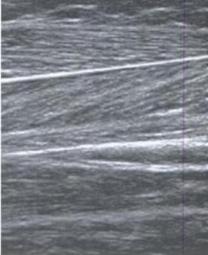

Zur Verdeutlichung:

li. ein normaler Muskel re. geschädigter Muskel meines Sohnes

mit normaler Struktur wattebauschartige Struktur